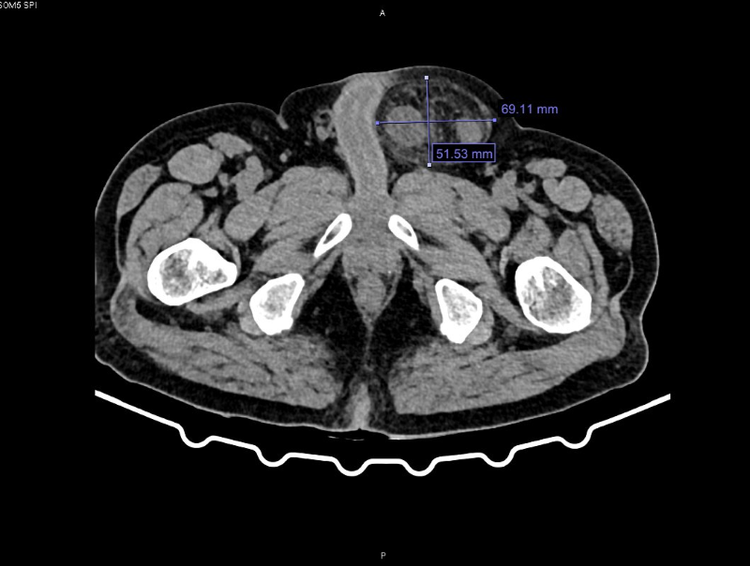

Qua thăm khám và chụp cắt lớp vi tính, các bác sĩ chẩn đoán bệnh nhân bị thoát vị bẹn trái nghẹt. Hội chẩn đánh giá đây là biến chứng phức tạp và nguy hiểm của thoát vị bẹn do ruột bị chui xuống lỗ thoát vị và kẹt lại gây tắc nghẽn, thiếu máu nuôi.

hoai-tu-dai-2.png

Hình ảnh khối thoát vị bẹn trái nghẹt qua phim chụp cắt lớp vi tính - Ảnh BVCC